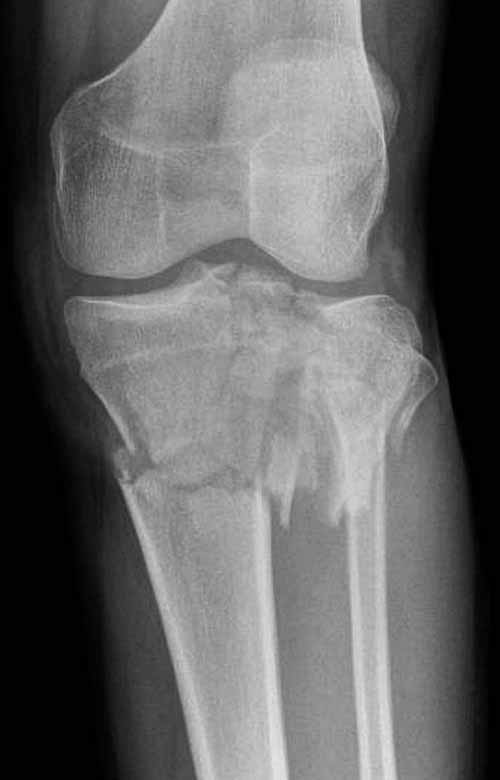

"участок некроза кожных покровов (см. фото), поэтому латеральная мыщелковая пластина не подойдет, а медиальных пластин у фирм-производителей нет. Пациент может приобрести современный имплант, но какой?"

Двухколоннный перелом тибиал плато с вовлечением проксимального диафиза. Внутрисуставной компонент без смещения, и такой перелом можно лечить любым из описанных методов, о которых говорят наши коллеги.

Как понял, аппарат Илизарова не рассматривается предпочтительным для фиксации методом, хотя на фоне отека было бы идеальным для данного перелома. Для пластины требуется идеальная кожа, иначе наличие “суперсовременных имплантов” не поможет, и могут развиться серьезные осложнения.

В основном пластины рассчитаны на латеральную поверхность, потому что с латеральной стороны больше мягкотканая подушка, а также через латеральную колонну проходит ось конечности, что немаловажно в удержании оси от деформации.

Частая ошибка, когда фиксацию двух колонного перелома проводят одиночной пластиной, т.е с одной стороны, и такая фиксация не удерживает, происходит вторичноое смещение. Необходимо нейтрализовать второй пластиной или дополнительным наружным фиксатором.

Кстати, коллеги правы для уточнения характера перелома надо делать Компьютерную Томографию.